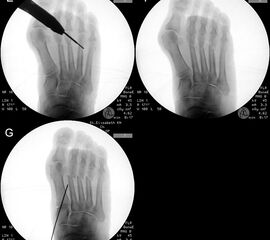

Zum Lesen der Bildbeschreibung und zur Vollansicht bitte die Bilder anklicken.

In unserer prospektiven Studie wurden 10 Patienten (8 Frauen und 2 Männer; Ø Alter 58 ¼ Jahre) mit einem symptomatischen Hallux valgus bei Pes adductus und Metatarsalgie mittels einer Lapidusarthrodese und einer lateralisierenden DMMO versorgt. Die Fusion des TMT-I-Gelenkes erfolgte offen mittels einer winkelstabilen, plantaren Platte. Alle zusätzlichen distalen Eingriffe (DMMO, Isham-OT, Akin-OT, Kleinzehenkorrekturen) wurden in minimalinvasiver Technik durchgeführt. Die Patienten wurden nach 6 Monaten klinisch und radiologisch nachuntersucht.

Der präoperative AOFAS-Score betrug 41,5 Punkte und konnte postoperativ auf durchschnittlich 86,2 Punkte verbessert werden (p<0,005). Der IMW reduzierte sich von Ø 16,7° (8,5°-20,3°) präoperativ auf Ø 7,14° (6,1°-9,5°) (p<0,005). Ebenso konnte der HVW von präoperativ Ø 45,2° auf postoperativ Ø 9,4° (p<0,005) korrigiert werden. Durch die Durchführung der modifizierten, lateralisierenden DMMO veränderte sich der präoperative VAW von Ø 23° (19,3°-33,5°) auf Ø 15,6° (13°-17,2°; p<0,004).